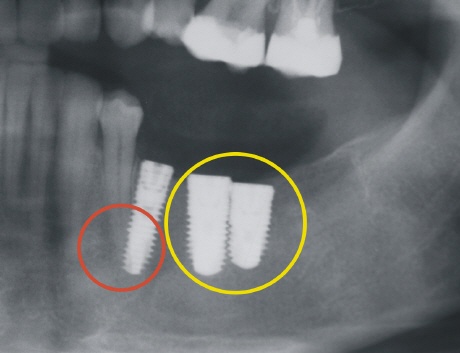

Die Schädigung von Nachbarwurzeln ist immer eine Folge fehlender Planung. Weder die Position der Implantate zueinander, noch die Implantatachse sind in diesem Fall richtig bestimmt worden. Auf dem Bild oben links sieht man, wie der Zahn durch das Implantat verletzt wurden (roter Kreis). Dies hatte zur Folge, dass der "angebohrte" Zahn mit "seinem Leben zahlen" musste und eine Wurzelfüllung benötigte (roter Pfeil).

Das Röntgenbild oben zeigt zwei viel zu dicht beieinander liegende Implantate (gelber Kreis) und ein von der Implantatachse ungünstiges Implantat, welches eine natürliche Zahnwurzel verletzt.